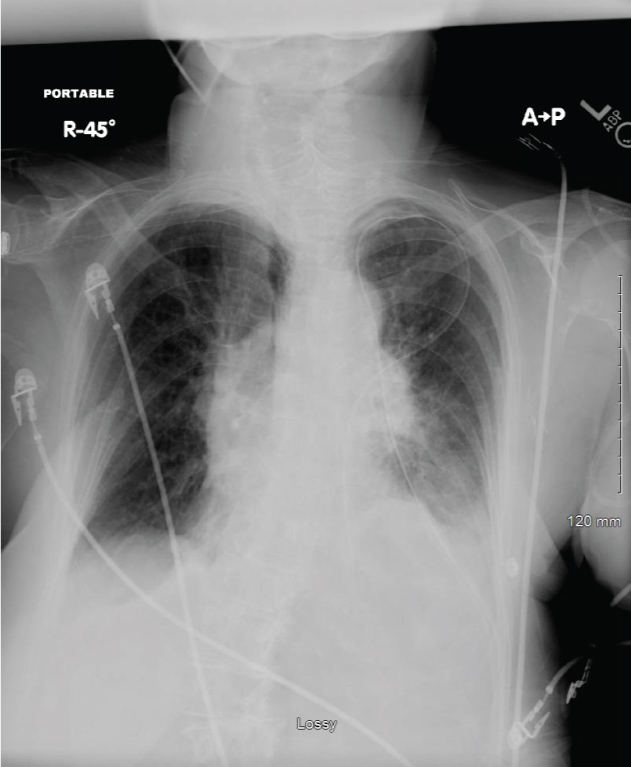

Smoking is the primary cause of emphysema which makes it a preventable illness. Diaphragm weakness due to medical intervention most commonly occurs as a result of physical trauma to the phrenic nerves or diaphragm muscle. Surgical treatment is an option for more advanced cases or if breathing becomes so impacted daily life is affected.

You may not need any treatment. Depending on the severity of injury to the diaphragm some doctors recommend non-surgical options to treat the breathing issues associated with diaphragm weakness and paralysis.

The rise in intraabdominal pressure further increases intrathoracic and lung volume by pushing the lower rib cage outward. In severe cases when there is no simple treatment that can relieve dyspnea your doctor may prescribe morphine. Diaphragmatic dysfunction caused by transverse myelitis or leukemic infiltration of the cervical spinal cord in a patient with leukemia and shortness of breath. Diaphragmatic plication a surgical procedure that pulls the diaphragm down by introducing a repeated series of continuous sutures across the diaphragm and pulling the muscle taut. A bedside fan or open window with a breeze are also simple but very effective treatments to lessen dyspnea. Depending on the severity of injury to the diaphragm some doctors recommend non-surgical options to treat the breathing issues associated with diaphragm weakness and paralysis. P E Pulmonary embolism.